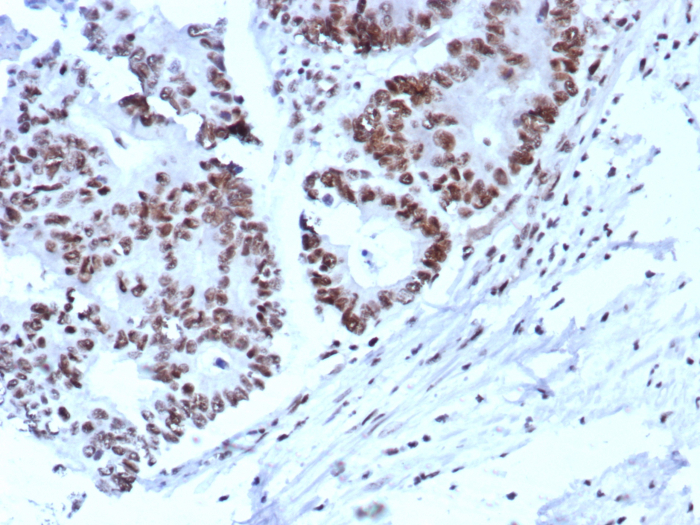

IHC analysis of formalin-fixed, paraffin-embedded human bladder. Strong nuclear staining using p57 Kip2 antibody (KIP2/8572) at 2ug/ml in PBS for 30min RT.

IHC analysis of formalin-fixed, paraffin-embedded human colon. Strong nuclear staining using p57 Kip2 antibody (KIP2/8572) at 2ug/ml in PBS for 30min RT.